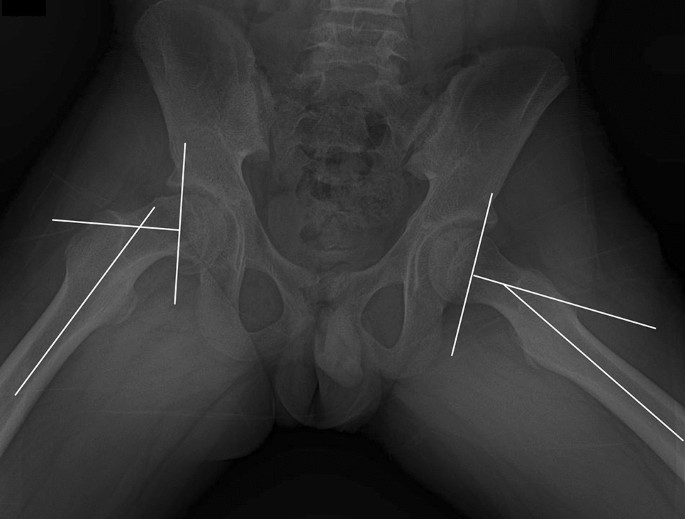

LLD was determined on full-length standing anteroposterior hip-to-ankle radiographs at skeletal maturity. The leg length was measured from the center of the femoral head to the superior border of the talus. LLD was recorded as a positive value when the affected side was longer than the unaffected side. LLDs were stratified into four groups based on cutoffs from previous literature30: no LLD (< 5 mm), small LLD (5 mm ≤ LLD < 10 mm), moderate LLD (10 mm ≤ LLD < 15 mm), and large LLD (≥ 15 mm). The articulotrochanteric distance (ATD) was also measured from supine anteroposterior hip projections at skeletal maturity (Fig. 4)29. Perpendiculars to the longitudinal axis of the femoral diaphysis was drawn at the level of the proximal limit of the femoral head and at the tip of the greater trochanter. The ATD was given a positive sign if the proximal limit of the femoral head was situated proximally to the tip of the greater trochanter; otherwise, it was negative. Articulotrochanteric distance difference (ATDD) was calculated as the healthy side minus the side with SCFE. Radiologic assessments were performed by two orthopedic residents who were blinded to the study details.